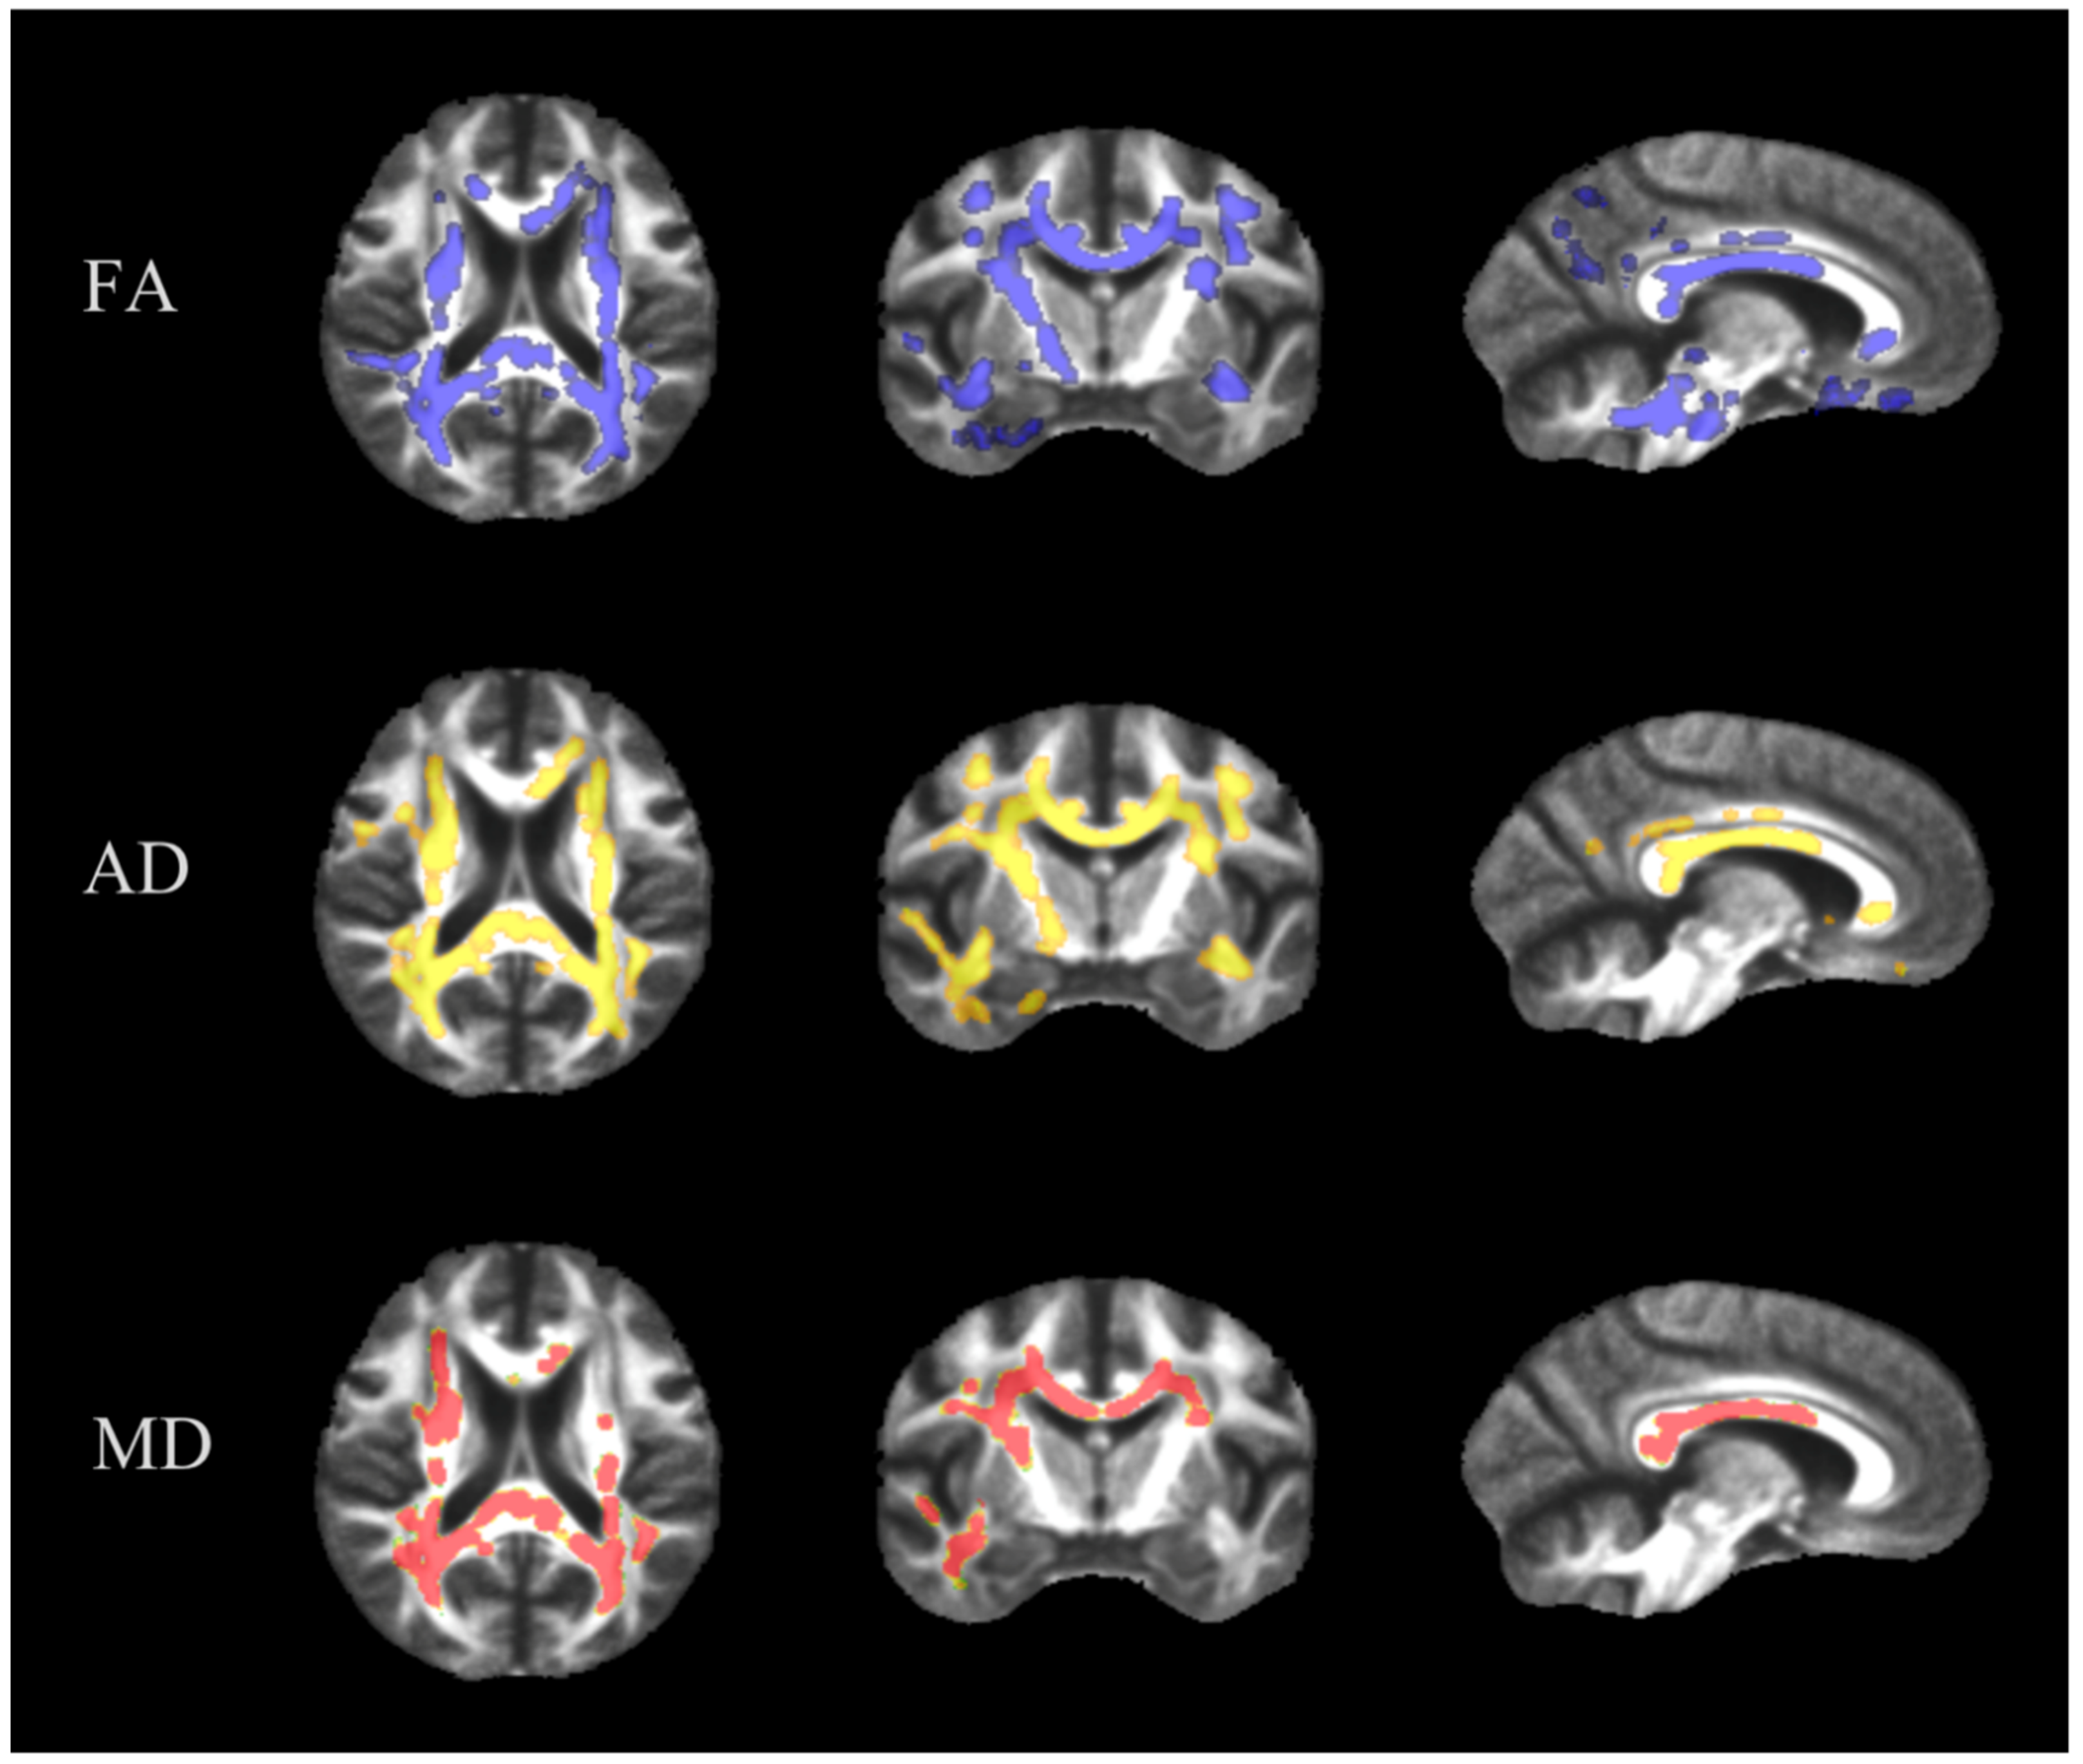

3.1. TBSS